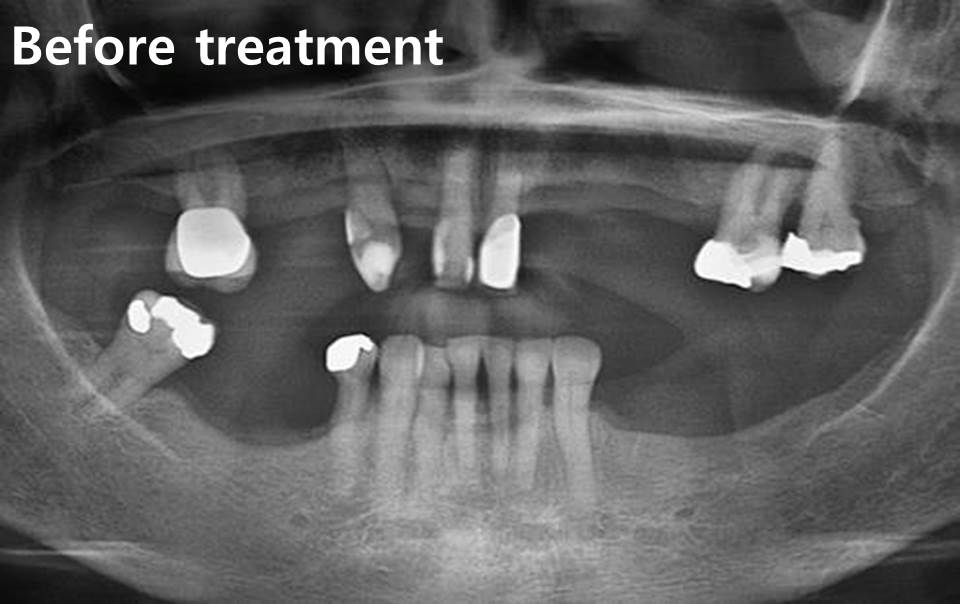

This case presents full mouth teeth replacement with All-on-4 concept treatment.

Healthy Australian female patient, 59 years old, came to BFCdental (Bangkok, Thailand) for making new full mouth teeth replacement.

She choose all remaining teeth extraction and All-on-4 concept treatment for her treatment option because of her affordable budget, and she need to complete full mouth treatment within 1 trip, 14 days.

This case presents full mouth teeth replacement with All-on-4 concept treatment. We use 4 dental implants and 5 dental implants to support lower & upper fixed hybrid denture. 4 tilted distal implants in all of quadrants had been placed for avoiding anatomical structures. We had used 3D-surgical guide with NEO-NAVIGUIDE kit drilling in upper jaw which is compromised bone width in most of area. After upper implants placement, we use buccal graft with sticky bone & CGF (concentrated growth factor) for guided bone regeneration.